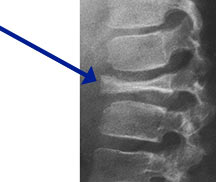

- • The work-up often consists of a physical examination, X-rays, CT scans, MRI, and sometimes bone scans are required.

Radiographic imaging is used to help form a diagnosis. These include X-Ray, MRI, CT and Bone Scans.

An example of an Eosinophilic Granuloma MRI is shown.